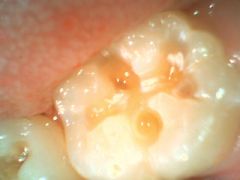

光重合型CRで治療

二次カリエス

(一度治した虫歯がまた虫歯になる事)

- シーラント部から虫歯になった例です。